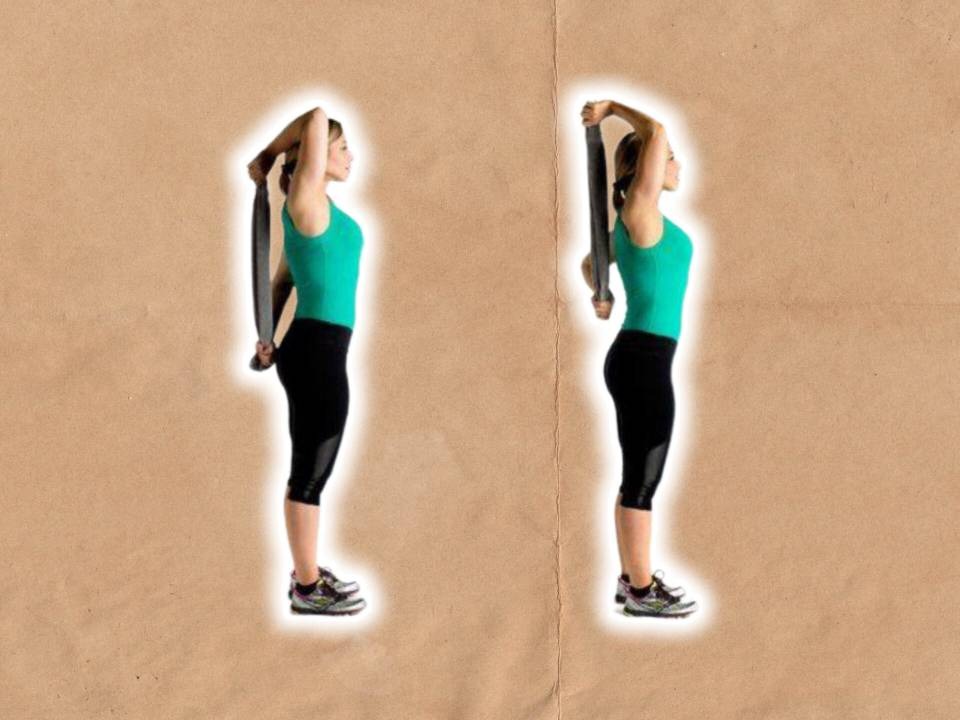

تمرین Codman، تمرین Pulley، تمرین Towel، تمرین Wall climbing و تمرین Shoulder wheel از مهم ترین های تمرین های شانه یخ زده زیر نظر درمانگر است.

تمرین Pulley. بهتراست قرقره پشت سر بیمار وصل شود.

تمرین Towel. بیمار با دو دست حوله را در پشت سر می گیرد، یک دست بالا و یک دست پایین.